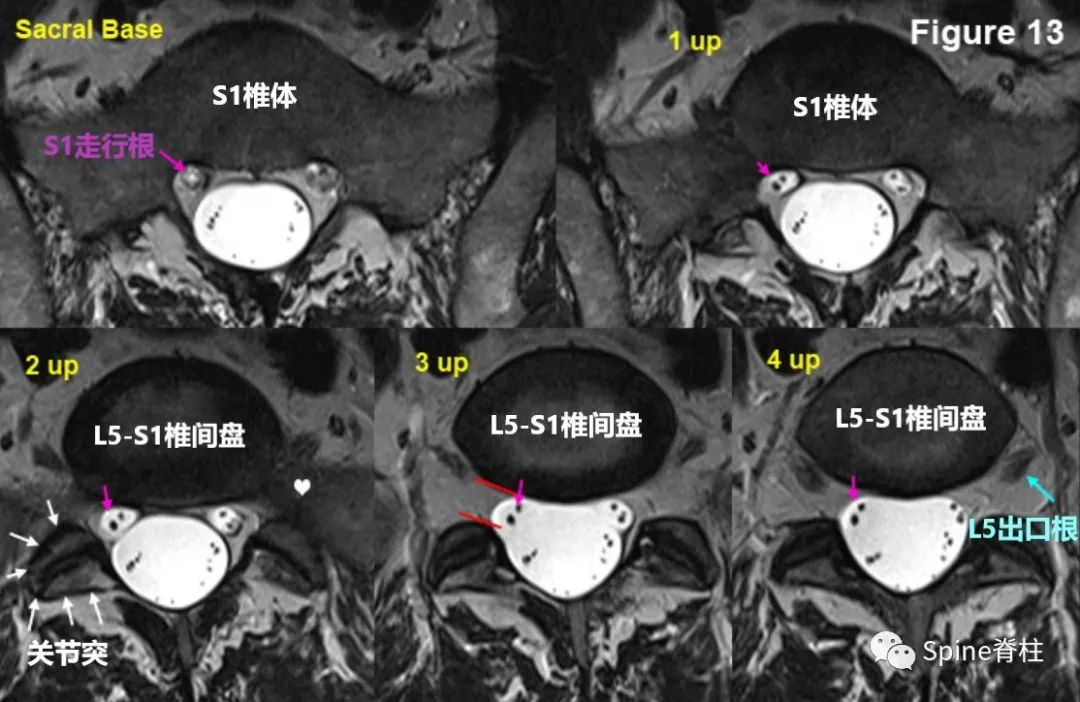

MRI从S1椎体层面向上连续扫描,至4up的L5/S1椎间盘水平。在2up处可以看到右侧关节突(白色箭头),3up中S1走行根刚开始从硬膜囊中发芽形成独立囊鞘。4up可明确看到L5/S1椎间盘。其实,从2up开始就看到部分L5/S1椎间盘。

从L5/S1椎间盘层面继续向上,并连续扫描至L4/5椎间盘,此患者L4/5椎间盘呈黑椎间盘。注意标注的各出口根和走行根